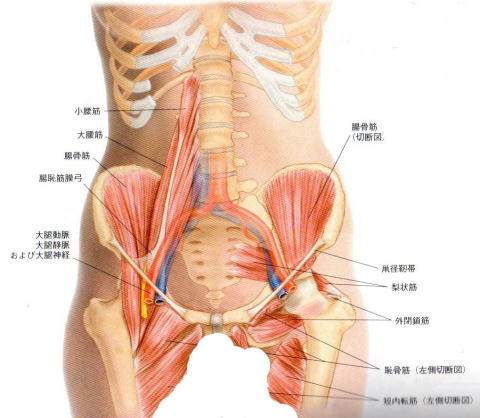

【腰痛の原因】 体をそると腰が痛い場合、様々ある原因の中から2つご紹介致します。 1、【鼡径部(そけいぶ)周辺の筋肉・血管・神経などがお互いにくっついてしまっている】 鼡径部には腸腰筋(ちょうようきん)=大腰筋+腸骨筋といわれる筋肉があり、その周辺には血管や神経、骨との摩擦を防ぐためにクッションの袋(滑液包)などがあります。 腸腰筋は腰の骨から太ももの骨についている筋肉ですので、周辺の組織(血管・神経・滑液包)とくっついてしまうと結果的に腰痛につながる事があります。 2、【S状結腸や盲腸などの腸の動きが悪くなっている】 腸は骨盤の関節である仙腸関節との関係がある為、腸の動きが悪ければ結果的に腰痛につながる場合があります。 当院では、これらの症状に対して慎重かつ極めて軽い力で、くっついている部分をはがしていきます。 よくマッサージなどで強い刺激を受けている方には「こんな刺激でよくなるの?」と言われますが、ここが原因で腰痛が起こっているのであ れば、極めて軽い力でも確実に効果はでます。(ちなみに力の入った指先では組織がゆるんだなどの感覚は確実に鈍くなりますし、組織の判 別も難しくなります。) 一般の方に覚えておいてほしい事は、鼡径部にある筋肉の表面には大きな血管・神経などがあるという事です。不必要な強い刺激はこれらの組織を痛めてしまいます。 「強い刺激・痛い刺激=効果がある」と思っている方は気を付けて下さね! 腰痛・ひざ痛、首などの関節の痛みは【関節の痛み専門院】トータルボディサポートEBMまでご相談下さい! トータルボディサポート EBM 住所 〒862-0971 熊本県熊本市中央区大江6-21-8白井ビル1F TEL 096-366-9555 当院Facebookはこちら http://on.fb.me/1StrBpJ